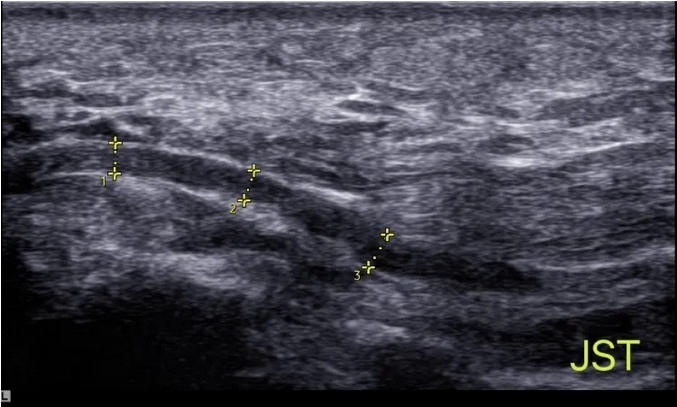

肌腱在超声图像中的表现

3.4 神经病变的“领航员”

肌骨超声还可以用于评估神经病变,如神经卡压综合征、神经瘤等。它能够显示神经的形态和周围结构的关系,为神经病变的诊断和治疗提供重要信息。

超声图像清晰显示神经